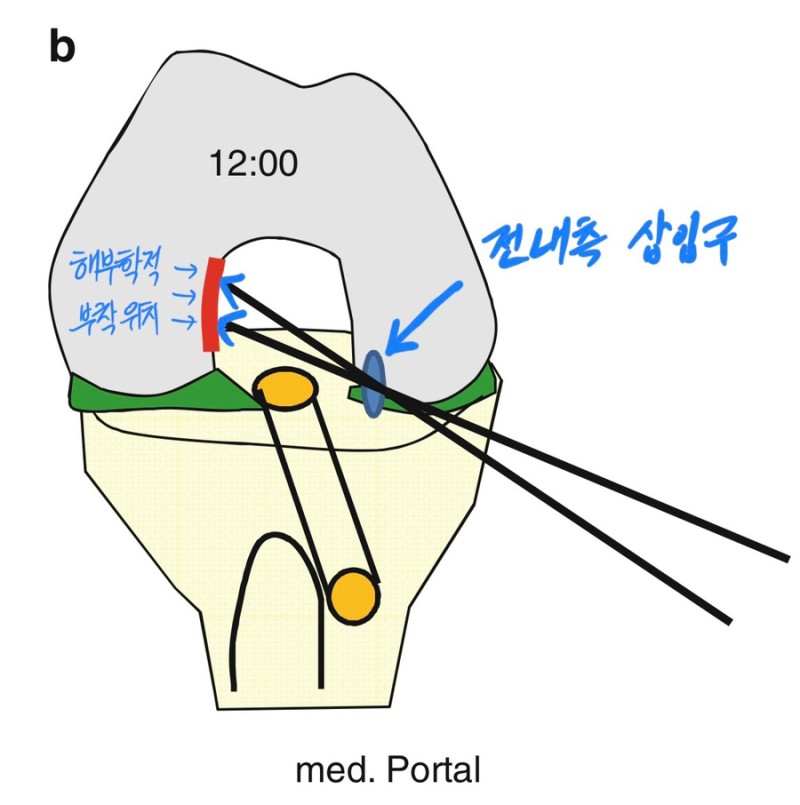

- 전내측 삽입구 술기 (AM portal technique)

경경골 술기를 통해 해부학적 위치를 정확하게

복원하기 어렵기 때문에, 이를 해결하기 위해 나온 방법이

전내측 삽입구 술기입니다.

경골 터널을 통하지 않기 때문에, 전내측 삽입구를 통해

전방십자인대가 무릎에 붙는 해부학적 위치에서 터널을

뚫을 수 있습니다.

-전내측 삽입구 술기의 단점

다만 문제는, 이렇게 전내측 삽입구를 통해서

터널을 뚫게 되면, 시작점은 해부학적인 위치에

잡을 수 있지만, 무릎뼈 자체의 모양때문에

터널의 방향에는 제한이 걸리게 되는데,

이 때문에 전내측 삽입구 술기에서는

대퇴 터널의 길이가 다른 방법에 비해

가장 짧아집니다.

문제는 터널의 길이가 짧아지는 만큼, 터널을 통과하는

인대가 터널 안에 접촉하는 면적이 좁아지기 때문에

인대의 안정성이 떨어진다는 단점도 있습니다.